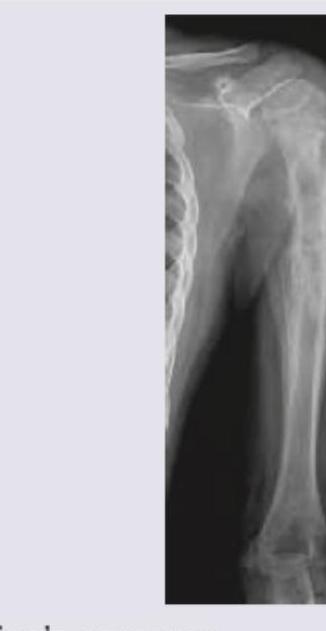

A 16-year-old boy presents with pain and swelling around the knee for 3 months. X-ray of the affected region is shown below. What is the most likely diagnosis?

Explanation: ***Osteosarcoma*** - **Osteosarcoma** is the most common primary malignant bone tumor, typically affecting the **metaphysis** of long bones in adolescents and young adults [1,2]. - Radiographically, it often presents with a **sunburst appearance** or **Codman's triangle** due to periosteal reaction [1]. *Ewing's sarcoma* - **Ewing's sarcoma** is a malignant small round blue cell tumor, often presenting with an **onion-skin appearance** on X-ray due to lamellated periosteal reaction [3]. - It commonly affects the **diaphysis** of long bones and flat bones, and is associated with the **t(11;22) translocation** [3]. *Giant cell tumor* - **Giant cell tumor** is a benign but locally aggressive tumor, typically found in the **epiphysis** of long bones, especially around the knee [4]. - It is characterized by numerous **osteoclast-like giant cells** and has a characteristic **soap-bubble appearance** on imaging [4]. *Enchondroma* - **Enchondroma** is a benign cartilaginous tumor that arises within the **medullary cavity** of bone, most commonly in the small bones of the hands and feet [3]. - It is typically asymptomatic and discovered incidentally, often appearing as a **well-circumscribed lucent lesion** with calcifications [3]. **References:** [1] Kumar V, Abbas AK, et al.. Robbins and Cotran Pathologic Basis of Disease. 9th ed. Bones, Joints, and Soft Tissue Tumors, pp. 1200-1202. [2] Cross SS. Underwood's Pathology: A Clinical Approach. 6th ed. Common Clinical Problems From Osteoarticular And Connective Tissue Disease, pp. 673-674. [3] Cross SS. Underwood's Pathology: A Clinical Approach. 6th ed. Common Clinical Problems From Osteoarticular And Connective Tissue Disease, pp. 671-672. [4] Kumar V, Abbas AK, et al.. Robbins and Cotran Pathologic Basis of Disease. 9th ed. Bones, Joints, and Soft Tissue Tumors, pp. 1205-1206.